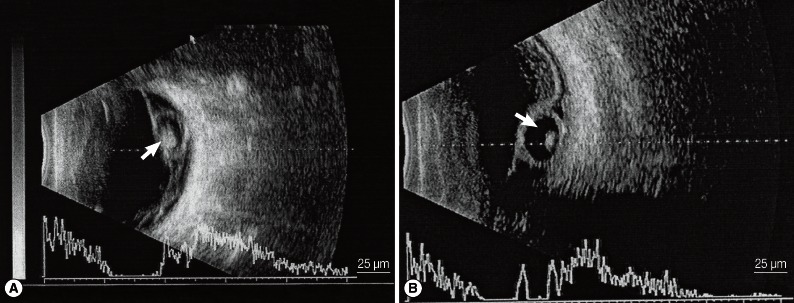

B ultrasonography revealed a round or oval vesicle-like echogenic mass in the vitreous chamber and a low-level echogenic mass in the vesicle, which indicated that the high-level echogenic spot was the scolex of the cysticercus (Fig. 2A). Through retinal detachment, a high-level echo in the membrane connected to the optic nerve as well as masses of varying echo levels caused by intravitreous bleeding and exudation were detected. For subretinal cysticercus, a strip echo connected to the optic nerve anterior to the cysticercus was detected (Fig. 2B).

Fig. 2

A) A cysticercus in the vitreous body shown by B ultrasonography. A round or oval vesicle-like echogenic mass can be seen in the vitreous body, and the high-level echo spot in it is the scolex (white arrow). B) A cysticercus in the subretinal region shown by B ultrasonography. An echo strip connected to the optic nerve is found anterior to the cysticercus (white arrow).

Fig. 2 A) A cysticercus in the vitreous body shown by B ultrasonography. A round or oval vesicle-like echogenic mass can be seen in the vitreous body, and the high-level echo spot in it is the scolex (white arrow). B) A cysticercus in the subretinal region shown by B ultrasonography. An echo strip connected to the optic nerve is found anterior to the cysticercus (white arrow).